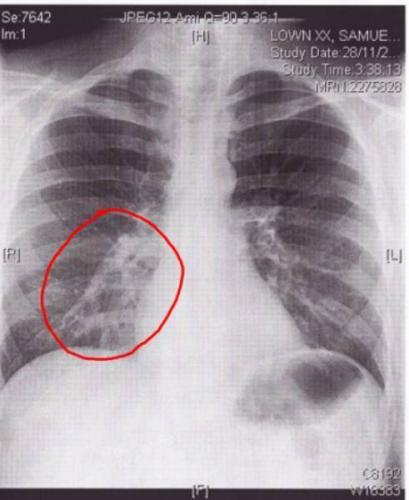

Самым результативным способом выявления болезни легких, является прослушивание новорожденного на присутствие хрипов в области грудной клетки и рентгеновское исследование.

Диагностика пневмонии у новорожденных проводиться с помощью рентгенологических и лабораторных исследований. Кроме того, верная постановка диагноза невозможна без учета клинических симптомов и данных анамнеза. Если у крохи выявлено воспаление легких, нужна госпитализация.

- Сегментарная – данный вид воспаления развивается после ОРВИ или другой вирусной инфекции. Выявить его можно только с помощью рентгеновского снимка, так как симптоматика очень незаметная и поставить диагноз на ее основании невозможно. Выздоровление, как правило, наступает на третью неделю после начала лечения.